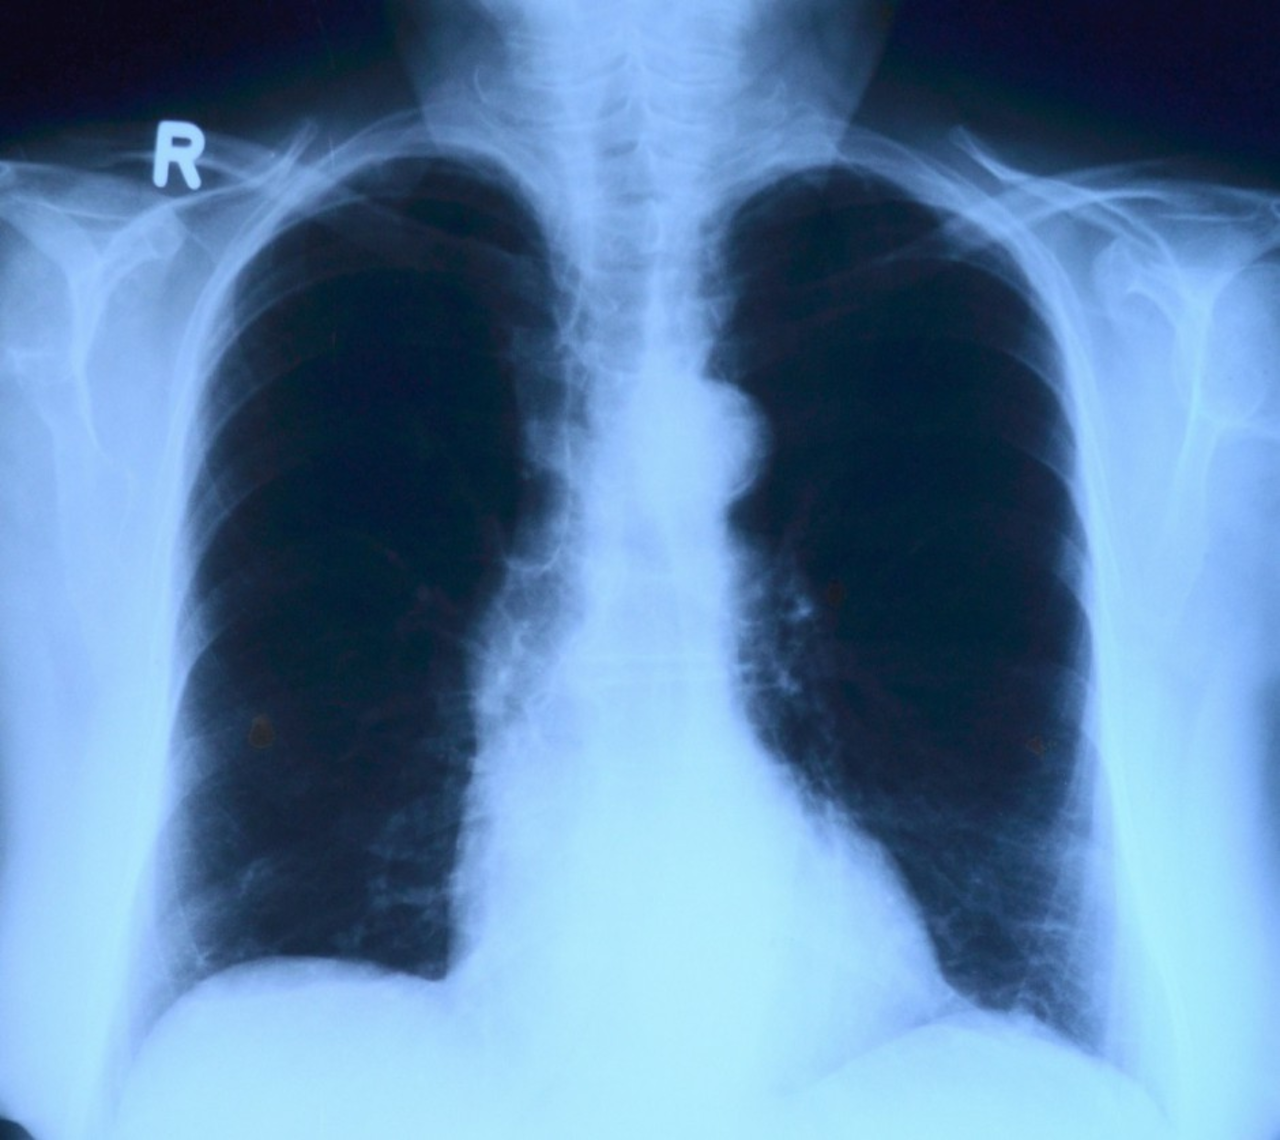

Kolejki do prześwietlenia płuc. Powodem koronawirus

Wzrosła liczba wykonywanych prześwietleń klatki piersiowej, z związku z tym trzeba obecnie dłużej na nie czekać. Wzrost spowodowany jest dużą liczbą pacjentów, którzy wykonują badania po przebytej chorobie Covid-19.

Jak informuje Małgorzata Pawlik, dyrektor przychodni Darimed w Kielcach, w placówce wykonywanych jest blisko 50 procent więcej badań niż przed pandemią koronawirusa. – Stanowczo wzrosła liczba wykonywanych prześwietleń. Czas oczekiwania wydłużył się z jednego dnia do nawet ośmiu dni roboczych.  Na każde prześwietlenie musi być skierowanie wystawione przez lekarza POZ bądź z prywatnej przychodni  - dodaje dyrektor.

Jak podkreśla dr Zbigniew Bajor, pulmonolog, osoby które przeszły Covid-19, a czują następstwa ze strony układu oddechowego, powinny wykonać prześwietlenie płuc. – Gdy po przebytej chorobie nadal występuje kaszel, duszności czy spadek wydolności oddechowej, a dodatkowo widoczny jest spadek saturacji, wskazane jest takie badanie. W przypadku wystąpienia zmian w płucach, które łączą się z występującymi objawami, może to wymagać pogłębionej diagnostyki  w postaci tomografu komputerowego – tłumaczy specjalista. – Warto się jednak skonsultować ze specjalistą, który oceni, na ile jest to konieczne – dodaje lekarz.